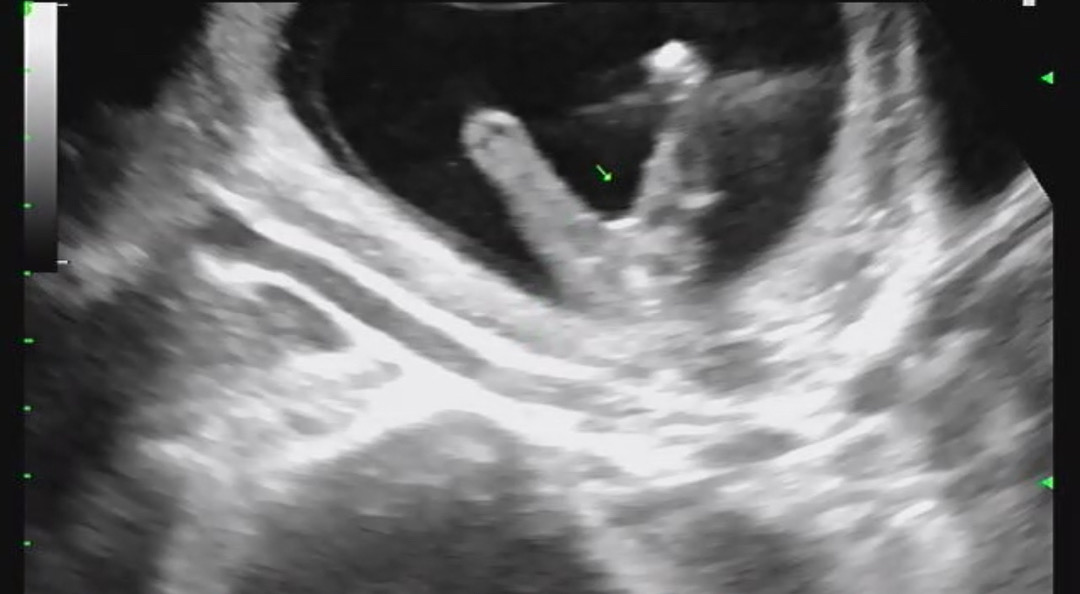

아들아들딸딸🥹

막내도 딸이라 너무좋네요 ㅎㅎㅎㅎㅎ 다들 성별 나오셨나요?